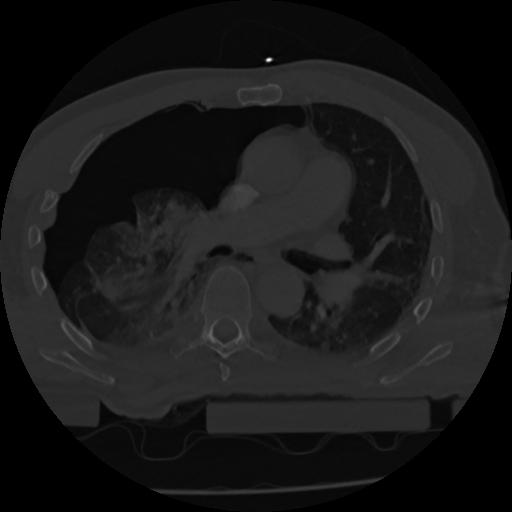

22 ANGIO,CE,Vol,0.5,ANGIO,,